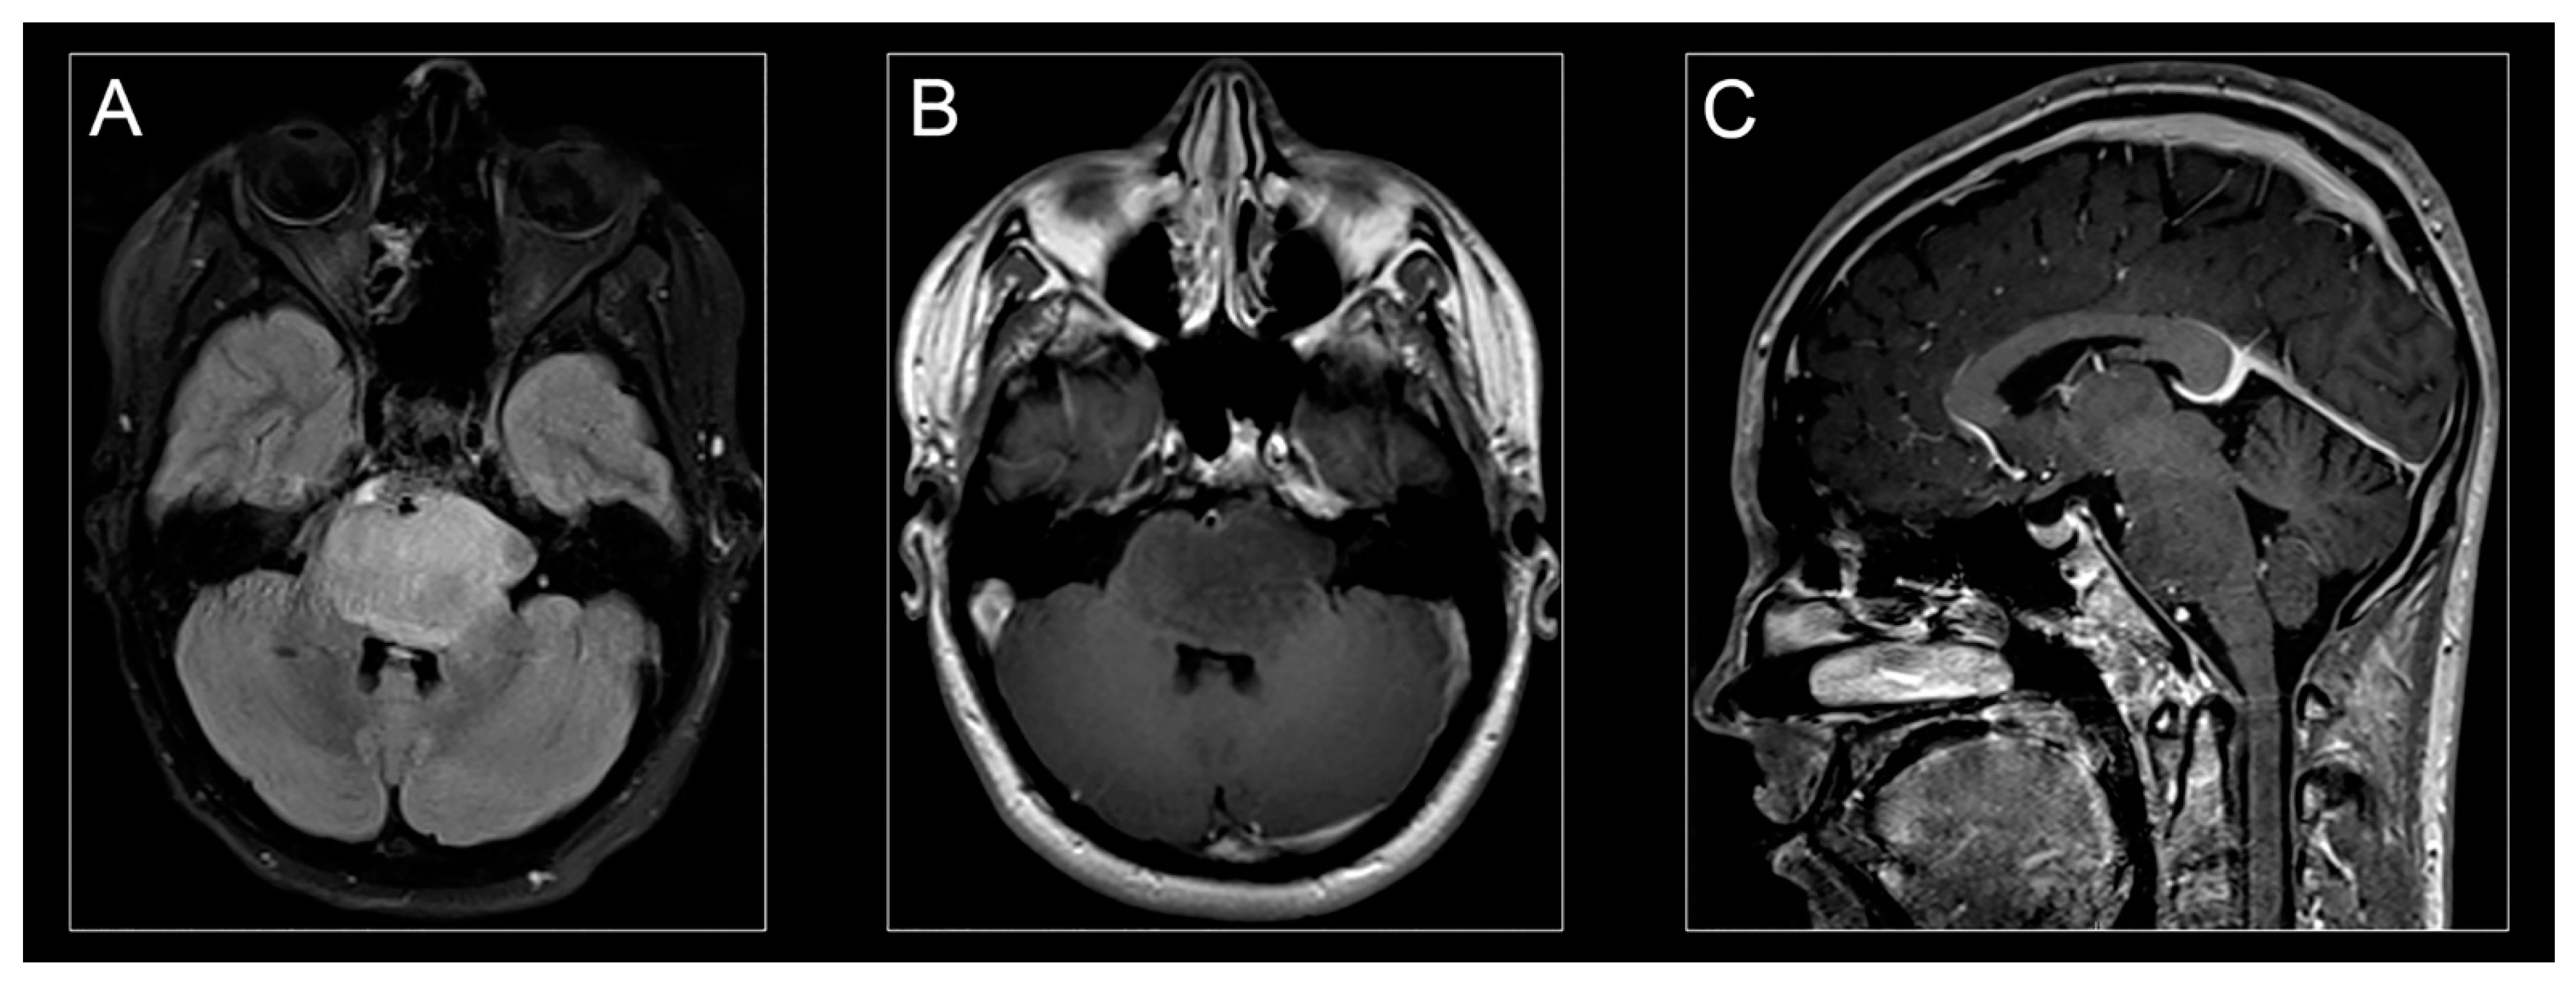

2.1. Characteristics and Presentation

2.2. Diagnosis